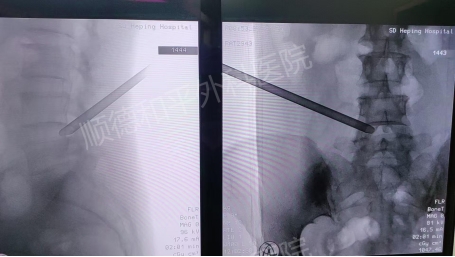

术前&术后

结合李女士的病情,张哉炯主任团队经过详细评估,为其制定了精准的治疗方案——微创经皮后路椎间孔镜下L4/5椎间盘髓核射频摘除术。

该术式是一种先进的微创手术,具有创伤小、恢复快等优势。手术通过椎间孔镜,在高清视野下精准定位突出的髓核组织,利用射频技术将其摘除,从而解除对神经的压迫,缓解疼痛麻木等症状。

李女士的手术历时2小时,过程顺利。术后当天,她的左下肢放射性麻木疼痛便明显缓解,腰部伤口仅有轻度疼痛,夜间睡眠正常。术后第1天,左下肢轻度胀痛较前显著减轻,已能自如卧床翻身活动,且无下肢麻木及乏力等不适。